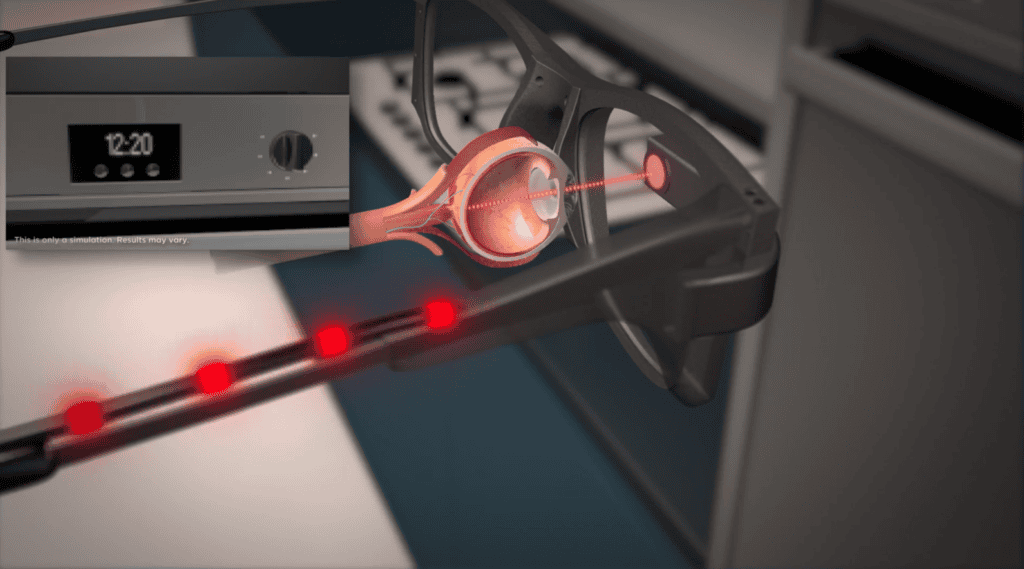

ชิป Prima ประกอบด้วยชิปสี่เหลี่ยมจัตุรัสขนาด 2 มม. ที่ถูกผ่าตัดวางไว้ใต้จอประสาทตา ตรงส่วนหลังสุดของลูกตา โดยใช้เวลาผ่าตัดนานถึง 80 นาที โดยจะใช้งานร่วมกับแว่นตาพร้อมกับกล้องที่จะบันทึกภาพ และส่งแสงอินฟราเรดไปยังชิป แล้วชิปดังกล่าวจะทำหน้าที่เสมือนแผงโซลาร์เซลล์ขนาดเล็ก ที่จะแปลงแสงเป็นการกระตุ้นไฟฟ้า และส่งไปยังสมอง จากนั้นสมองจะตีความสัญญาณดังกล่าวเป็นภาพ ซึ่งเป็นการเลียนแบบกระบวนการการมองเห็นตามธรรมชาติ

ซึ่งการทำงานของอุปกรณ์ของ Science Corporation แตกต่างจาก Neuralink และบริษัทอื่นๆ อีกหลายแห่งตรงนี้ บริษัทเหล่านั้นออกแบบการมองเห็นโดยข้ามดวงตาไปและใช้วิธีกระตุ้นคอร์เทกซ์การมองเห็นของสมองแทน